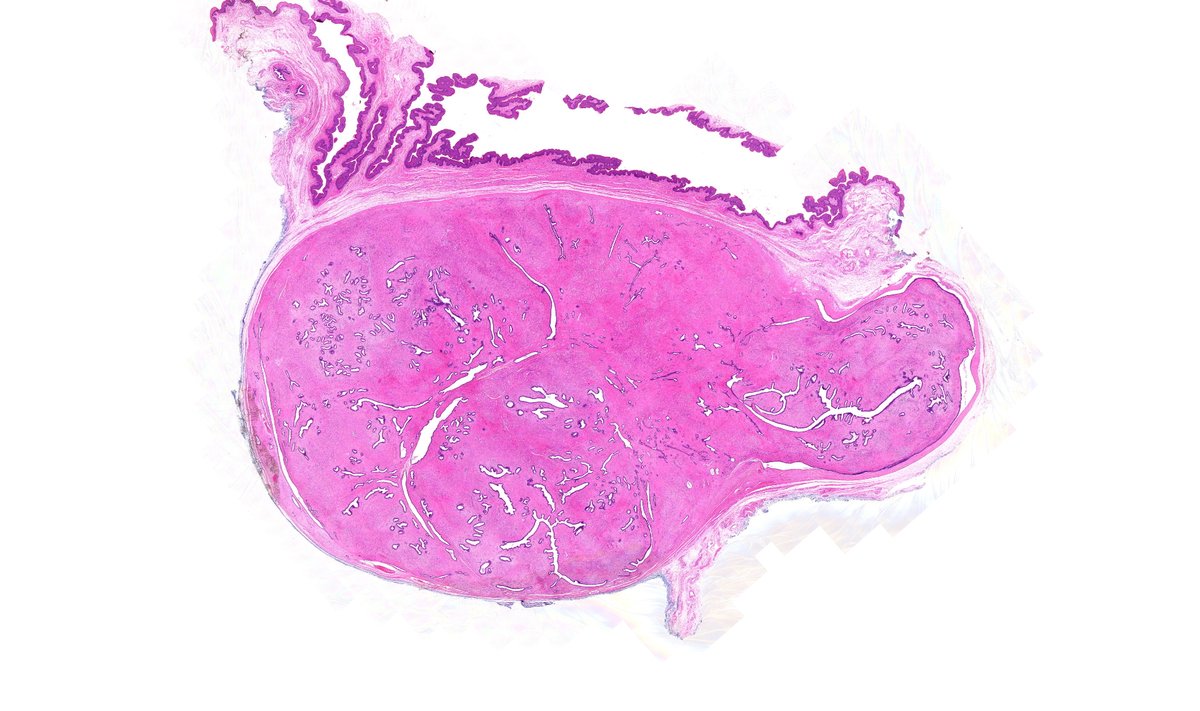

The Whipple specimen, one that requires good knowledge of the pancreaticobiliary anatomy. Here we can see how the tumor is present at the head of the pancreas narrowing the main pancreatic duct and causing obstruction.I hope this is helpful. #GIpath #PancreaticCancer